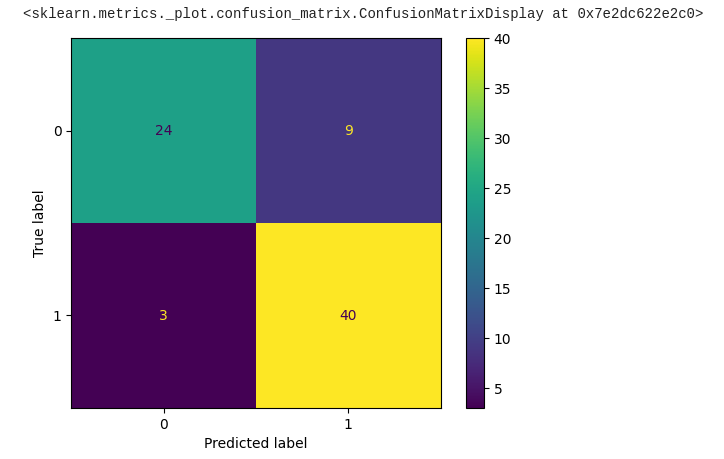

The following is a confusion matrix , which represents the above parameters:

First, we'll calculate the confusion matrix to get the necessary parameters:

With these values, we can now calculate an accuracy score:

One commonly tool used for evaluating classification models is the confusion matrix. Let's explore what a confusion matrix is and how it's used for model evaluation:

In a binary classification problem (two classes, for example, "positive" and "negative"), a confusion matrix typically looks like this:

Here's the code to plot the confusion matrix from the predicted data of our model:

Bravo! We've made significant progress toward obtaining the required output, with approximately 84% of the data appearing to be correct.